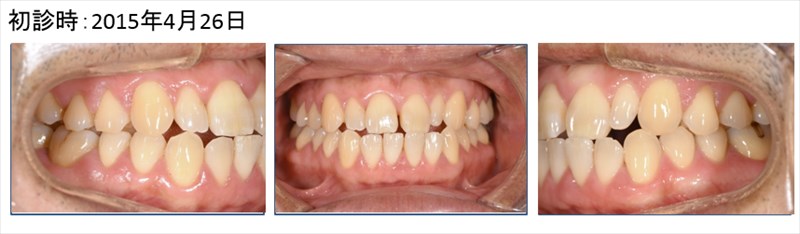

全顎的に歯周病も改善し喜んでおられました!!

歯茎の色もとても良い!!